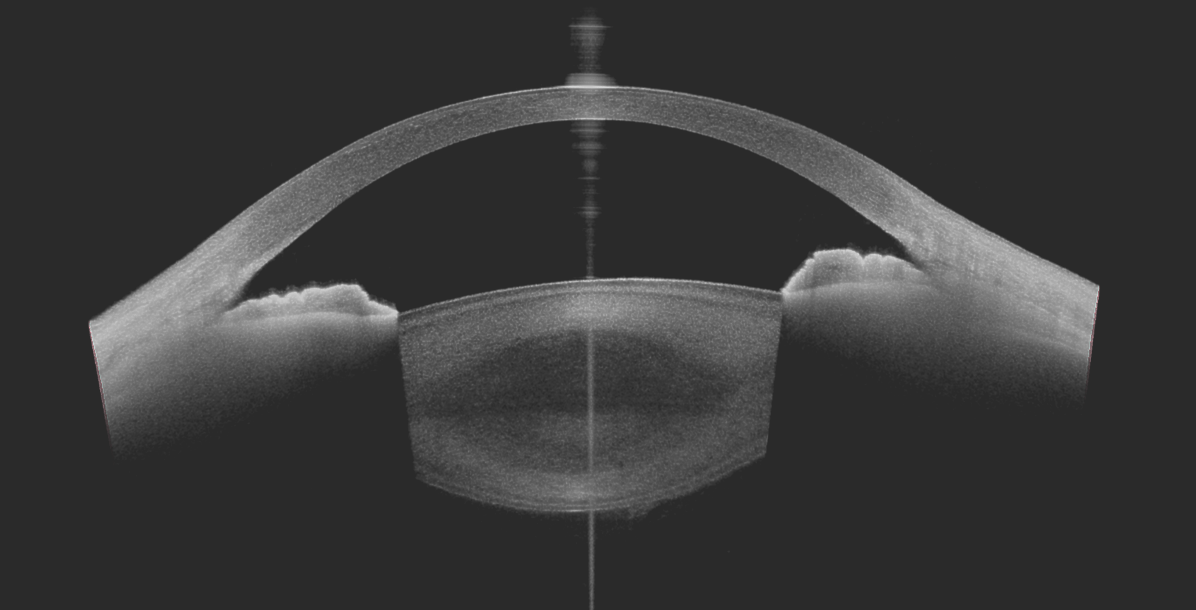

L'OCT du segment antérieur permet l'exploration de tout la partie antérieure de l’œil et de l'angle irido-cornéen.

Les coupes permettent ainsi une exploration de : la cornée, la chambre antérieure, l'iris, le cristallin.

Les mesures suivantes seront alors faites : épaisseur de la cornée, profondeur de la chambre antérieure, flèche cristallinienne, épaisseur du cristallin.